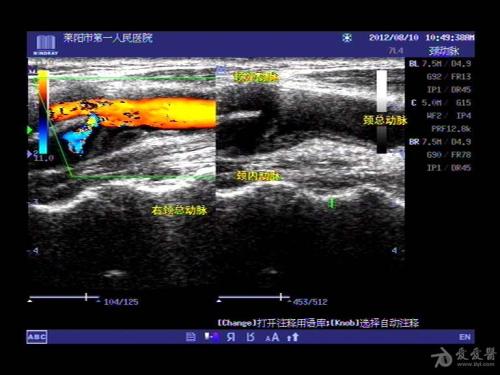

选用西门子生产的X300多普勒超声诊断仪,探头频率设定为7.5兆赫。超声诊断后,保存受检人员的图像,便于临床分析。考生选择仰卧姿势,并在双肩位置垫一个软枕头。头部位置以45度的角度倾斜到相反的位置。检查左右两侧的颈动脉。检测颈总动脉、颈总动脉分叉处、颈内动脉和颈外动脉斑块。在检测过程中,遵循自上而下的原则。密切观察颈总动脉内径和颈总动脉内膜中层厚度,并据此测量血管阻力指数。

本研究选取我院收治的60例糖尿病患者作为观察组,选取同期来我院体检的60名健康人作为对照组。彩色多普勒超声诊断后,观察组颈总动脉、颈总动脉分叉处、颈内动脉和颈外动脉斑块的发生率高于对照组,而颈总动脉内膜中层厚度明显厚于对照组,数据差异有统计学意义(p < 0.05)。然而,两组间颈总动脉内径无显著差异。由此可见,颈动脉粥样硬化的危险因素是糖尿病。在多次颈动脉检查中,彩色多普勒超声不会对患者造成创伤,能直观显示颈动脉壁本身的结构,能有效检测动脉粥样硬化斑块,并能正确评估动脉狭窄的程度和范围,这有助于早期发现病变血管,从而充分了解动脉硬化的程度和性质,评估心脑血管并发症造成的风险,还能利用检测结果作为预测数据来评估冠心病,表明彩色多普勒超声能为临床[7]提供正确的检测数据。